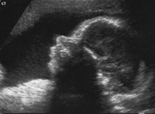

Prenatal Diagnostics / Ultrasound

- Malformation diagnostics

- Doppler sonography

- 3-D-Sonography